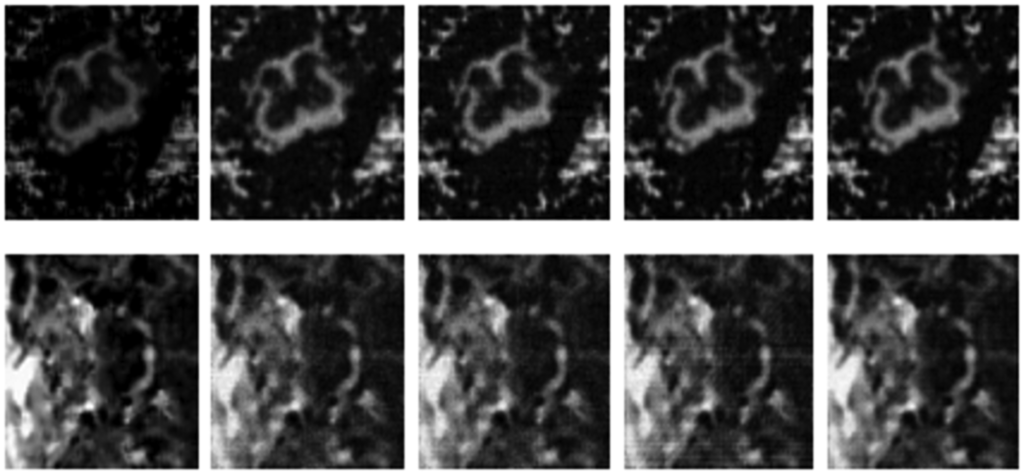

3.2. Qualitative Results

Numerical results do not always provide information about the qualitative nature of reconstruction. Thus, we provide reconstructed and difference images for visual inspection. Owing to limitations in space, we only show the results for 64 lines (this corresponds to a sampling ratio of 25%). Echo numbers 1, 5, 9 and 13 are shown in the following figures. In Figures 1 and 2, the ex vivo and in vivo reconstructed images are shown. In Figures 3 and 4, the difference images corresponding to ex vivo and in vivo imaging are shown respectively.

Looking closely at these figures, especially at the edges, one can see that the reconstruction quality progressively improves as one move from top to bottom. The worst results are obtained when the same Fourier map is used for all the echoes and simple row-sparse MMV recovery is used. The results improve slightly when rank-deficiency is introduced, but the improvement is only slight because the condition of incoherence is not satisfied when the same Fourier map is used for all the echoes. When different Fourier maps are used for the different echoes, the results from both group-sparse recovery and rank-deficient group-sparse recovery show improvement in the reconstruction quality; this is because of the better incoherence in the measurement operator. However, the best results are obtained when rank-deficient group-sparse recovery is used with different Fourier maps for different echoes.